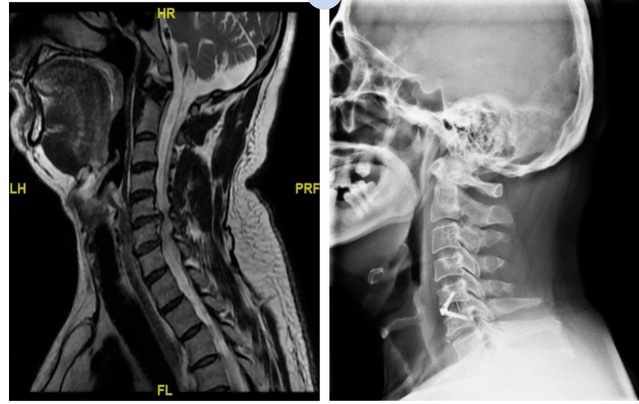

病例一

术后患者椎间隙高度恢复,生理曲度恢复,神经受压解除;头部胀痛,右上肢放射痛得到缓解。